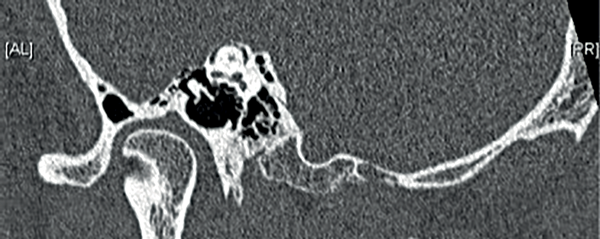

Computed tomography (CT) is the imaging modality of choice and is able to identify dehiscence, particularly if 0.5mm slices with reconstruction in Poschel and Stenver’s view (parallel and orthogonal to the direction of the SSC) are used (Figure 2). Scan findings must, however, be assessed in conjunction with clinical features because of the presence of dehiscence in asymptomatic individuals.

Figure 2: A high resolution oblique coronal reconstruction CT scan of the temporal bone

clearly demonstrating dehiscence of the superior semicircular canal.